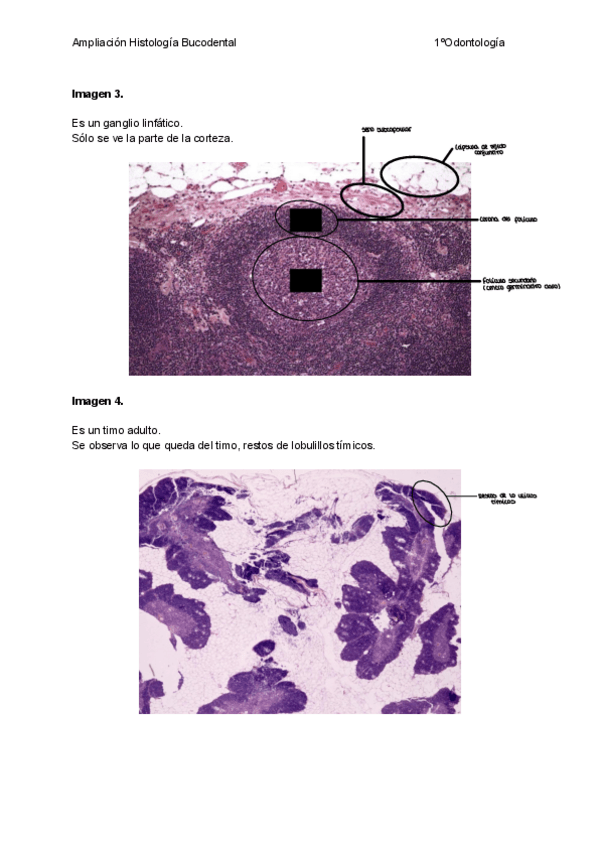

Imágenes de examen

Estas imágenes entraron en el examen